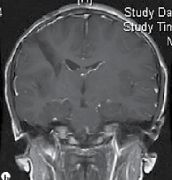

青少年鞍区/鞍上肿块增大会是脑瘤吗?

案例演示 一名有急性淋巴细胞白血病(ALL)缓解史的16岁男孩表现为头痛、上睑下垂、肌痛、疲劳以及下背部和骶骨麻木和疼痛加剧。初步检查,包括大脑的电脑断层扫描和核磁共振成像...